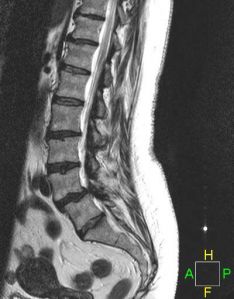

CERVICAL SPINAL STENOSIS

LUMBAR SPINAL STENOSIS